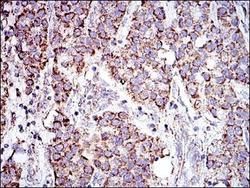

Supportive validation

- Submitted by

- Novus Biologicals (provider)

- Main image

- Experimental details

- Immunohistochemistry-Paraffin: Prohibitin Antibody (5H7) [NBP2-37563] - Immunohistochemical analysis of paraffin-embedded stomach cancer tissues using PHB mouse mAb with DAB staining.